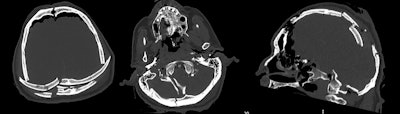

CT scans performed after a traumatic crush injury. The man was unloading a lorry during a storm when the contents fell on top of him.

CT scans performed after a traumatic crush injury. The man was unloading a lorry during a storm when the contents fell on top of him.Q: Why does someone have a PMCT and not just a traditional postmortem?